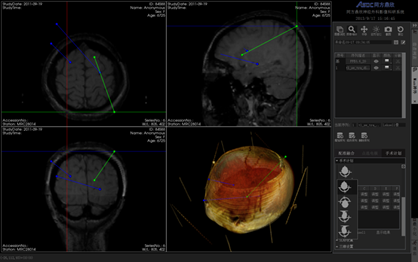

同方鼎欣専門映像製品シリーズは神経外科、整骨科、血管分析などの臨床科を対象にする診療補助、手術計畫、分析に関するソリューションであり、醫療映像の導入、二次元映像閲覧、三次元再構成、シリーズ校正融合、自動分割、自動計算、手術計畫などの機能を統合しています。臨床科の専門要求を満足する一方で、完璧、強力、信頼、便利なツールプラットフォームを提供します。

MPR、MIP、AveIP、MinIP;

三次元ボリューム描畫再構成(VR)、三次元面描畫再構成(SR);

融合(Fusion)、融合結果の三次元再構成;

複數検査と複數シリーズの座標マッチング、マニュアル/自動校正調整;

神経外科手術計畫モジュール;